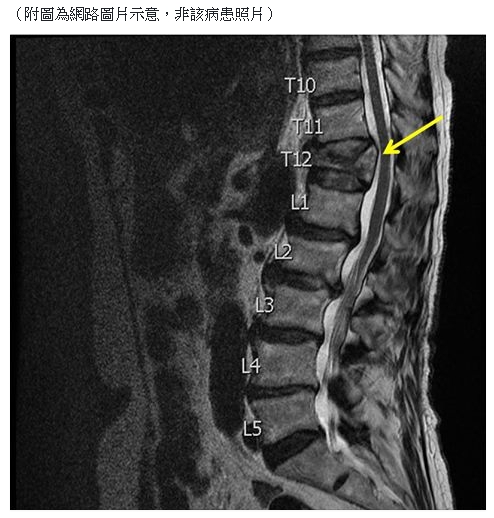

▲女病患脊椎因為舉重滿是傷痕(示意圖/翻攝自柯紹華臉書

桃園敏盛醫院神經外科主任柯紹華在臉書PO文表示,曾經有位因為長期背痛的女病患向他就診,一照X光卻嚇傻了,女病患的脊椎滿是陳年舊傷與不同程度的壓迫性骨折,他驚訝的和對方說:「光看這影像就知道妳一定很痛厚...」,女病患只是點了點頭,他又接著問:「可是妳這麼年輕脊椎就這麼多問題,過去是一直從事粗重的勞動工作嗎」,對方這才靦腆回應「喔,我從前是舉重國手,現在在工廠搬貨...」。